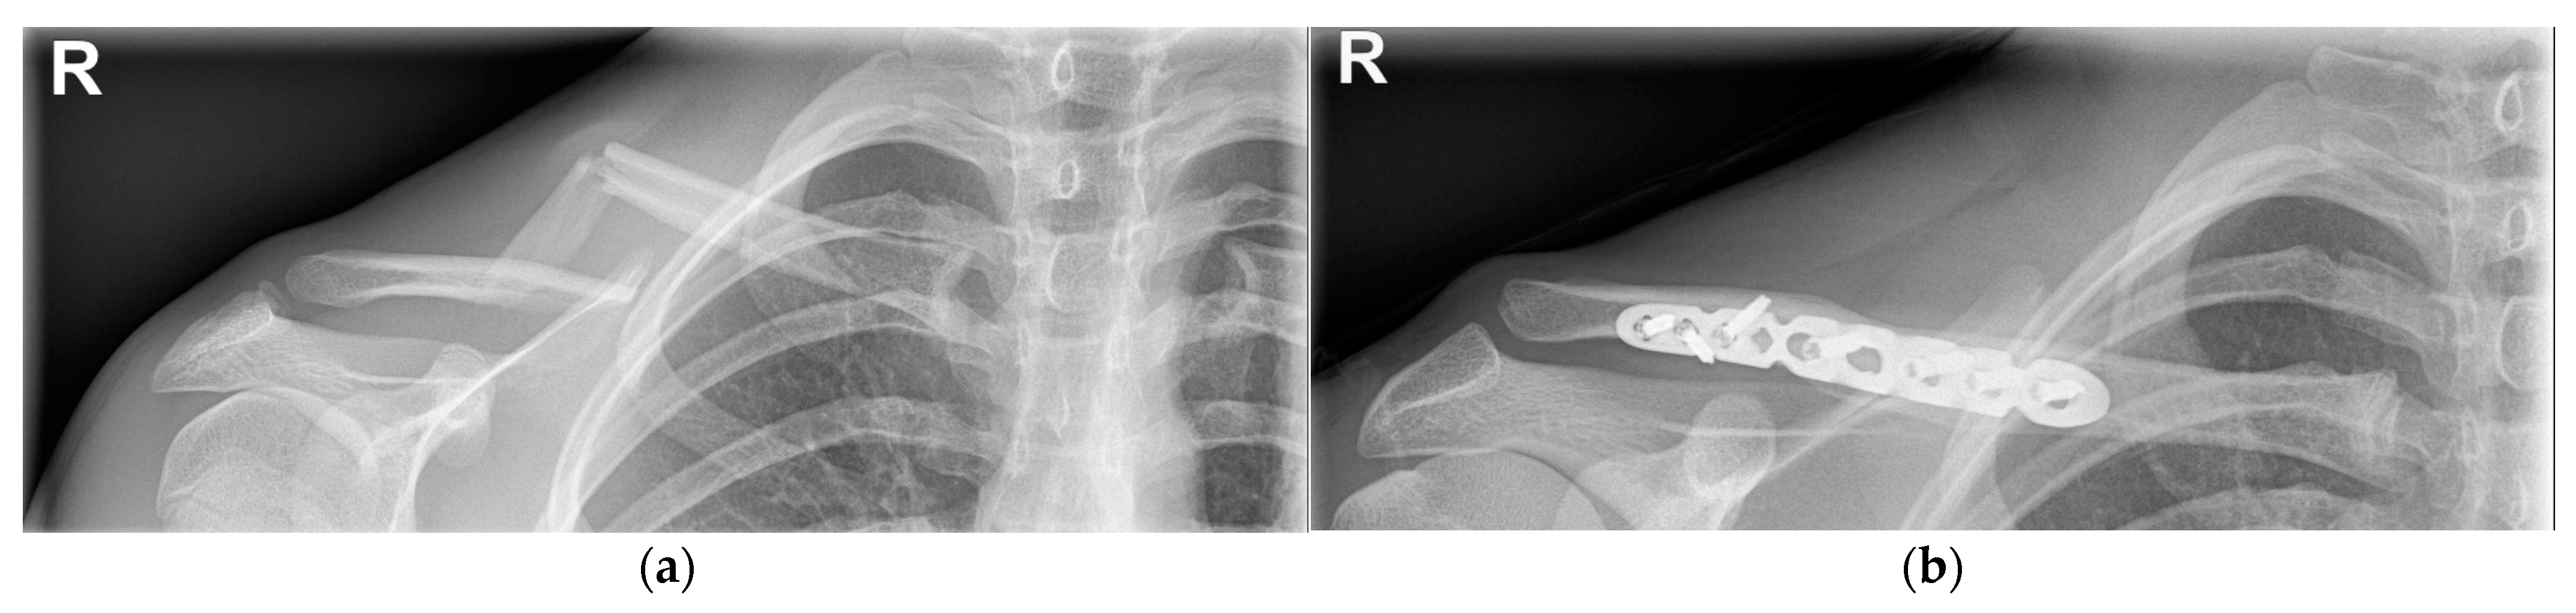

4.2.2. Operative Treatment